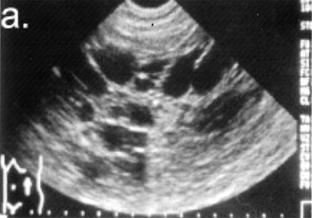

Ecografie abdominala |

Ficat de forma si dimensiuni normale, cu ecostructura omogena si ecogenitate nemodificata. Colecist cu peretii ingrosati

fara imagini de calculi. Vena porta, CBP, pancreas,

splina fara modificari. Rinichi drept, ax lung de |

Ficat cu ecostructura

neomogena. Pe toata aria de proiectie a sectiunii

hepatice, se vizualizeaza multiple formatiuni transonice, cu

diametre de la 0,5 la |

Ficat de forma si

dimensiuni normale cu ecostructura omogena si ecogenitate

nemodificata. Colecist cu peretii supli, fara imagini de

calculi. Vena porta, CBP, pancreas, splina, fara modificari.

Ambii rinichi usor mariti de volum, cu cateva formatiuni

transonice de dimensiuni de la 0,5 la |

nemodificata. Colecist cu peretii ingrosati, fara

imagini de calculi. Vena porta, CBP, pancreas, splina, fara

modificari. Ambii rinichi mariti de volum cu multiple

formatiuni transonice, cu diametre de la 0,5 la |